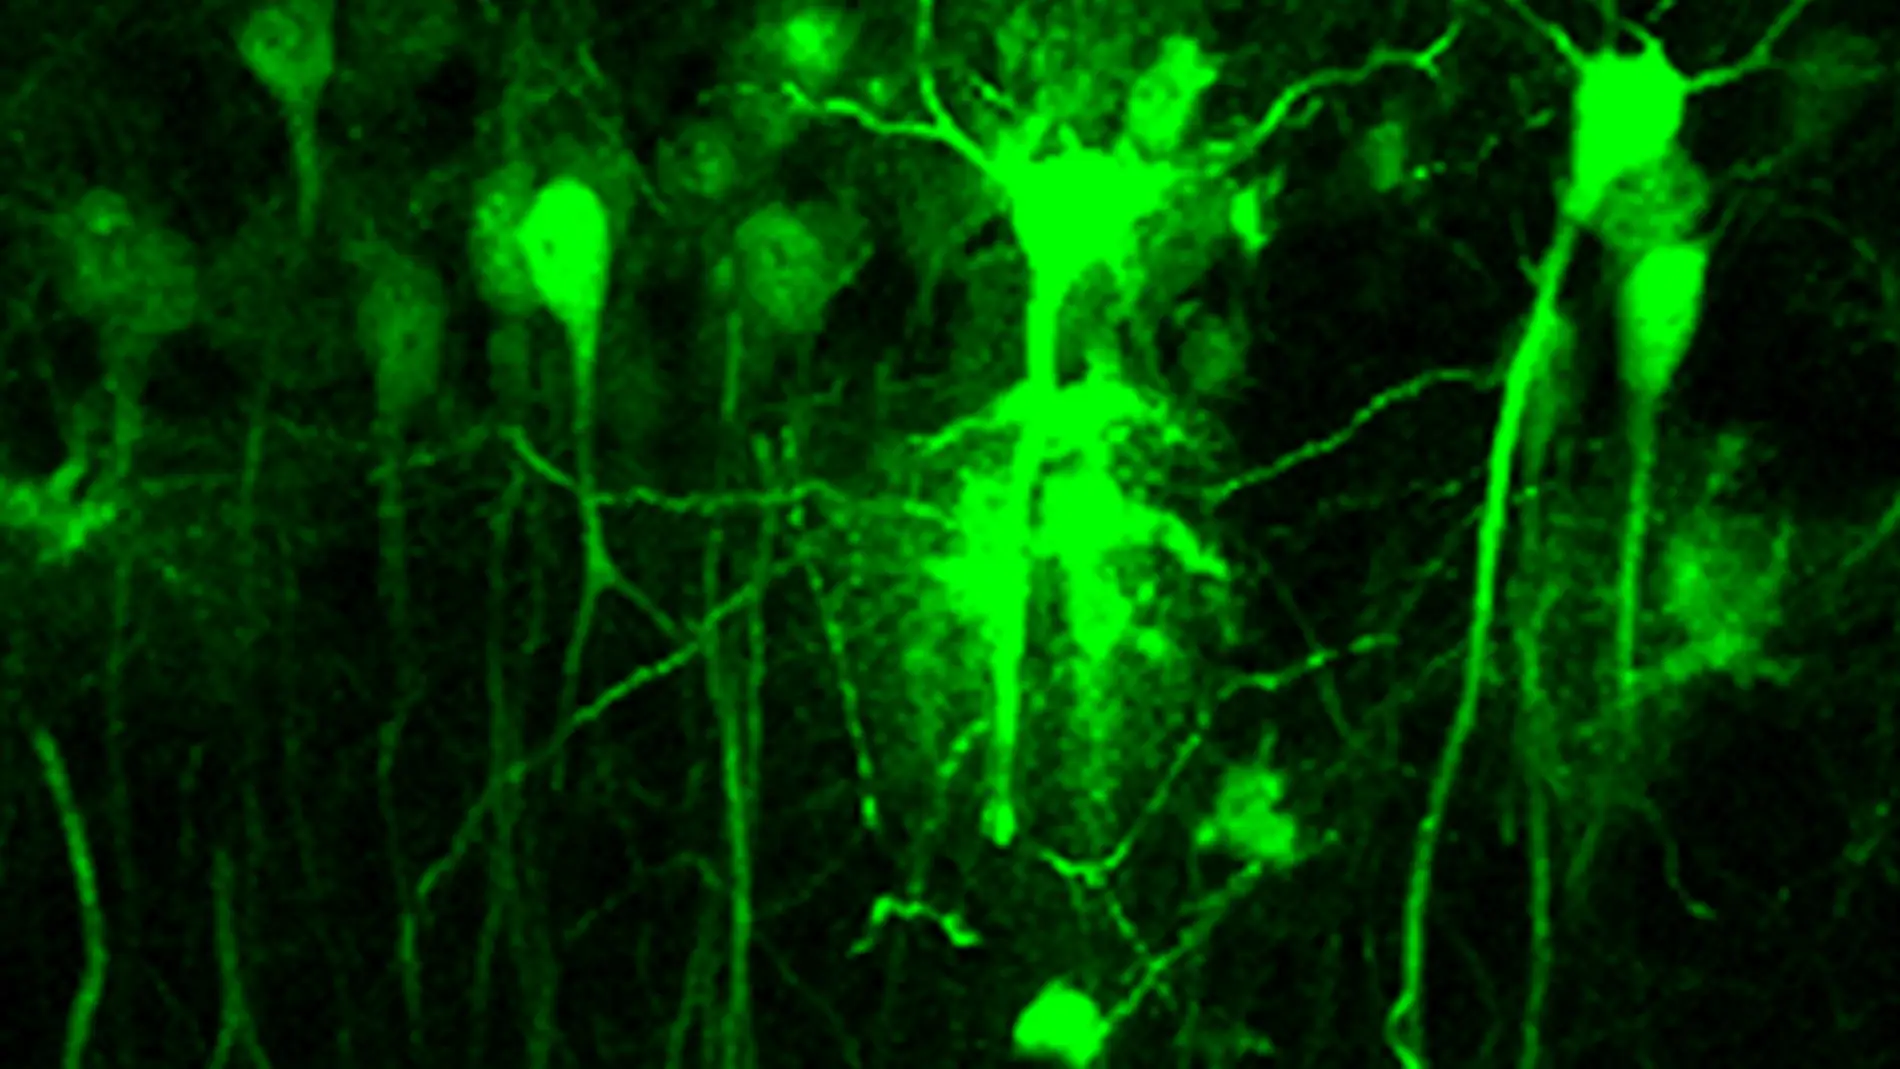

Un estudio liderado por científicos del Consejo Superior de Investigaciones Científicas (CSIC) y el Centro de Investigación Biomédica en Red sobre Enfermedades Neurodegenerativas (CIBERNED), en colaboración con la Universidad Pablo de Olavide (UPO), muestra que es imprescindible la presencia del receptor dopaminérgico D2 en las neuronas del hipocampo para que la dopamina –uno de los principales neurotransmisores cerebrales– pueda modular los cambios sinápticos responsables de la adquisición y la consolidación de la memoria.

Combinando el uso de un modelo genético de ausencia del receptor D2 con estrategias de manipulación genética, los investigadores han comprobado que la falta de este receptor reduce la plasticidad sináptica en el hipocampo

Combinando el uso de un modelo genético de ausencia del receptor D2 con estrategias de manipulación genética, los investigadores han comprobado que la falta de este receptor reduce la plasticidad sináptica en el hipocampo. El trabajo se publica en la revista Cerebral Cortex.